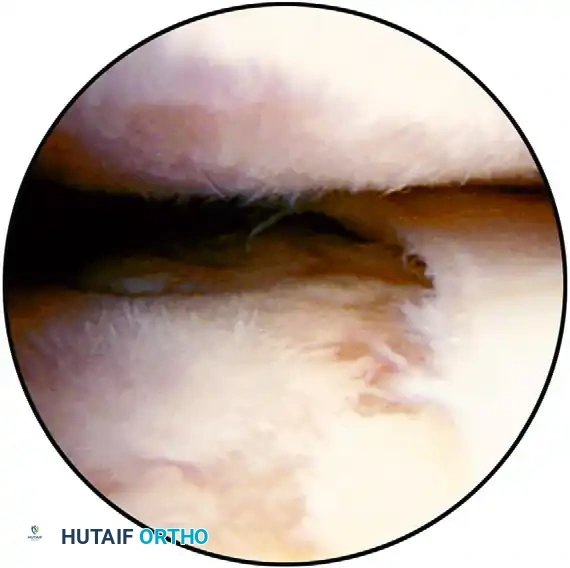

SPINOGLENOID CYST Surgical Diagram

FIGURE 52-52: Arthroscopic débridement and joint space evaluation. In cases of severe contracture or concomitant osteoarthritis, thorough visualization and debridement of the intra-articular space are necessary precursors to capsular release.